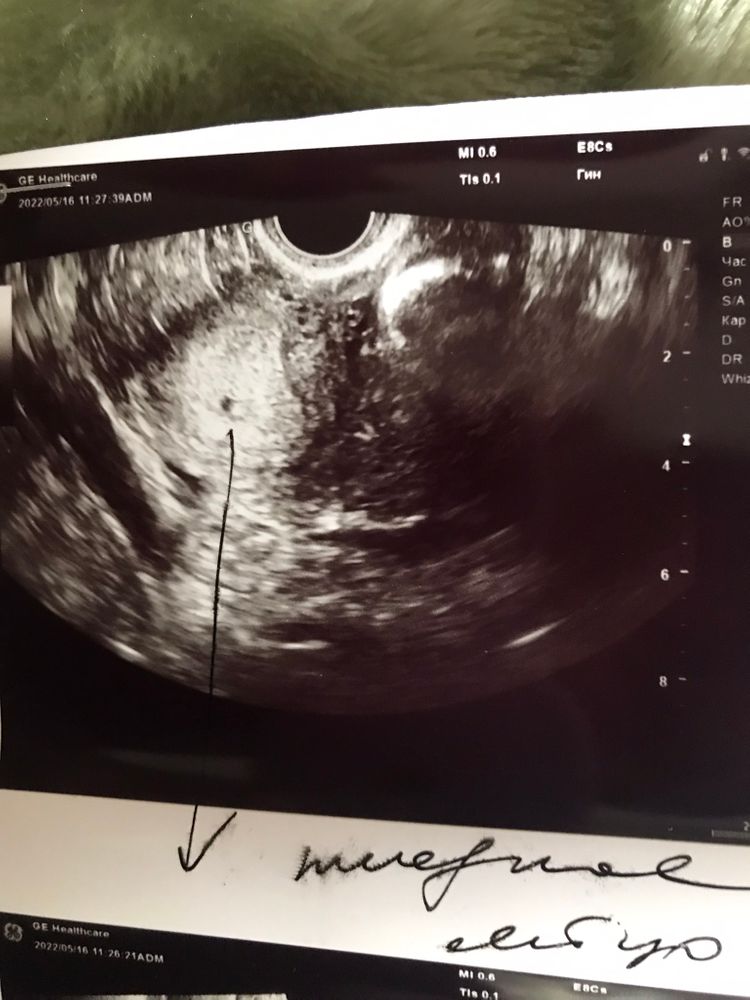

Судя по точке, срок совсем маленький) 2-3 недели думаю)

Милена , а на узи были когда хгч был сколько? 7125.6? Я бы могла предположить двойню, но на снимке только 1 точка, так что врядли) Но при таком хгч уже должно было быть больше на узи сведений. Важно когда именно делали узи и последний результат хгч) Гинекологу показали результат хгч и узи? Что сказала?

Женевьева, 14.05.2022. Хгч был 863.5 16.05.2022 пошла узи

Милена , а, тогда всё верно вам там увидели) Хгч вначале обоих беременность у меня тоже в 3-3,5 раза увеличивался (динамику смотрят по сдаче с интервалом 48 часов, раза 3 и дальше хватит уже) , после определённой цифры темп роста уменьшиться. Около 1000 единиц когда - видят пя маленькое в матке, когда больше 15-17 тысяч - уже сердцебиение можно услышать, это неделе на 7. Удачи)

В заключении смотрите, какой размер указали плодного яйца, по нему уже и можно нормально судить о сроке. Ну раз ставите значок "беременность" 3 недели, то значит и срок вам лучше знать 😉 Всё, что тут видно и как называют узисты - признаки ранней беременности и про срок ничего не говорят. Как подрастёт и получится померить ктр, то уже будет понятен точнее срок)

Милена , если 3 недели по плодному яйцу, то 5 акушерских недель (от начала последних месячных считают), этот срок в основном везде пишут (в кружочках на сайте тоже🤭)